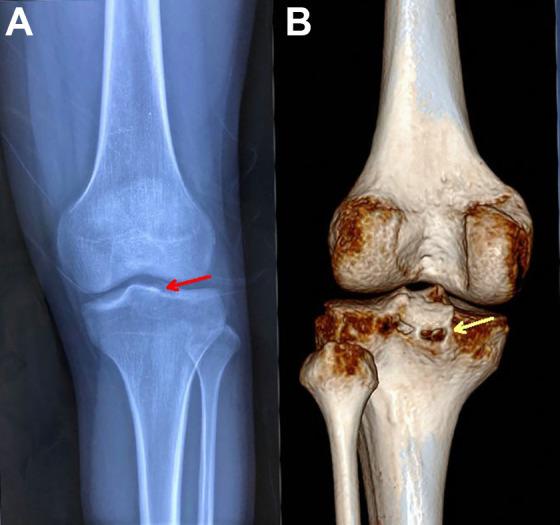

The optimal surgical treatment of delayed avulsion fractures of the posterior cruciate ligament (PCL) is still controversial.

From January 2013 to February 2017, we treated 15 patients with delayed tibial avulsion fractures of the PCL arthroscopically through posteromedial and posterolateral portals. The PCL and avulsion bone fragment were fixed with No. 2 nonabsorbable FiberWire sutures that were pulled out through a single tibial bone tunnel and fixed on a small Endobutton. Concomitantly, anatomic PCL augmentation reconstruction was performed, and the graft was pulled out through the same tunnel and fixed with an interference screw. Knee stability was assessed using the posterior drawer test, and the side-to-side difference was determined using a KT-1000 arthrometer with 134 N of posterior force at 30° of knee flexion. The International Knee Documentation Committee (IKDC) 2000 subjective form and Lysholm scale were used to evaluate clinical outcomes at follow-up. Overall, 12 patients were enrolled for analysis. The mean follow-up period was 34.4 months (range, 26-49 months).